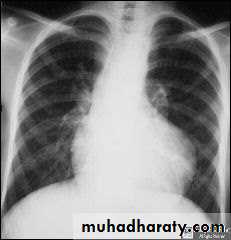

• 2.CxR.:

a.small VSD -> normal

b.large VSD -> cardiomegaly, dilated pulmonary vessels (plethoric lung)

A.CXR

Cardiomegaly of RV configuration

Round apex peak

Increase pulmonary marking

Chest X-ray: Cardiomegaly, plethoric lung, and prominent pulmonary conus.

• CXR : boat shaped heart , clear lung field , 20 % right sided aorta .